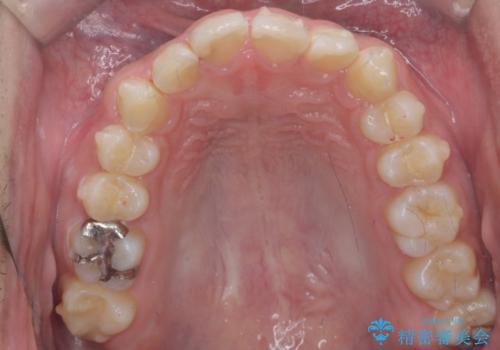

左のかみ合わせが1本分ずれていましたが、機能的には問題ないのでそのまま変えずに治療しています。

ずれている分を、上の歯を1本抜くか(ワイヤー矯正になります)、右上の奥歯を1本分後ろに送るか、そのまま前歯を並べるのかを選んでいただきました。

右のかみ合わせをそのままに、最小限の動かし方で見た目を改善しました。